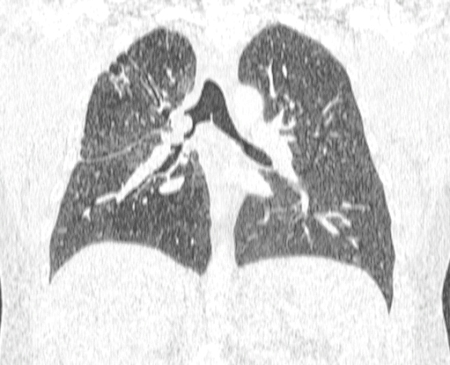

Злокачественная эндобронхиальная обструкция на мультидетекторной КТ: многопланая реконструкция в формате 2D (проекция минимальной интенсивности), демонстрирующая злокачественную обструкцию правого главного бронха

Из коллекций Хосе Фернандо Сантакруза, дипломированного врача, члена Американской коллегии специалистов в области торакальной медицины, DAABIP, и Эрика Фолка, дипломированного врача, магистра наук; используется с разрешения